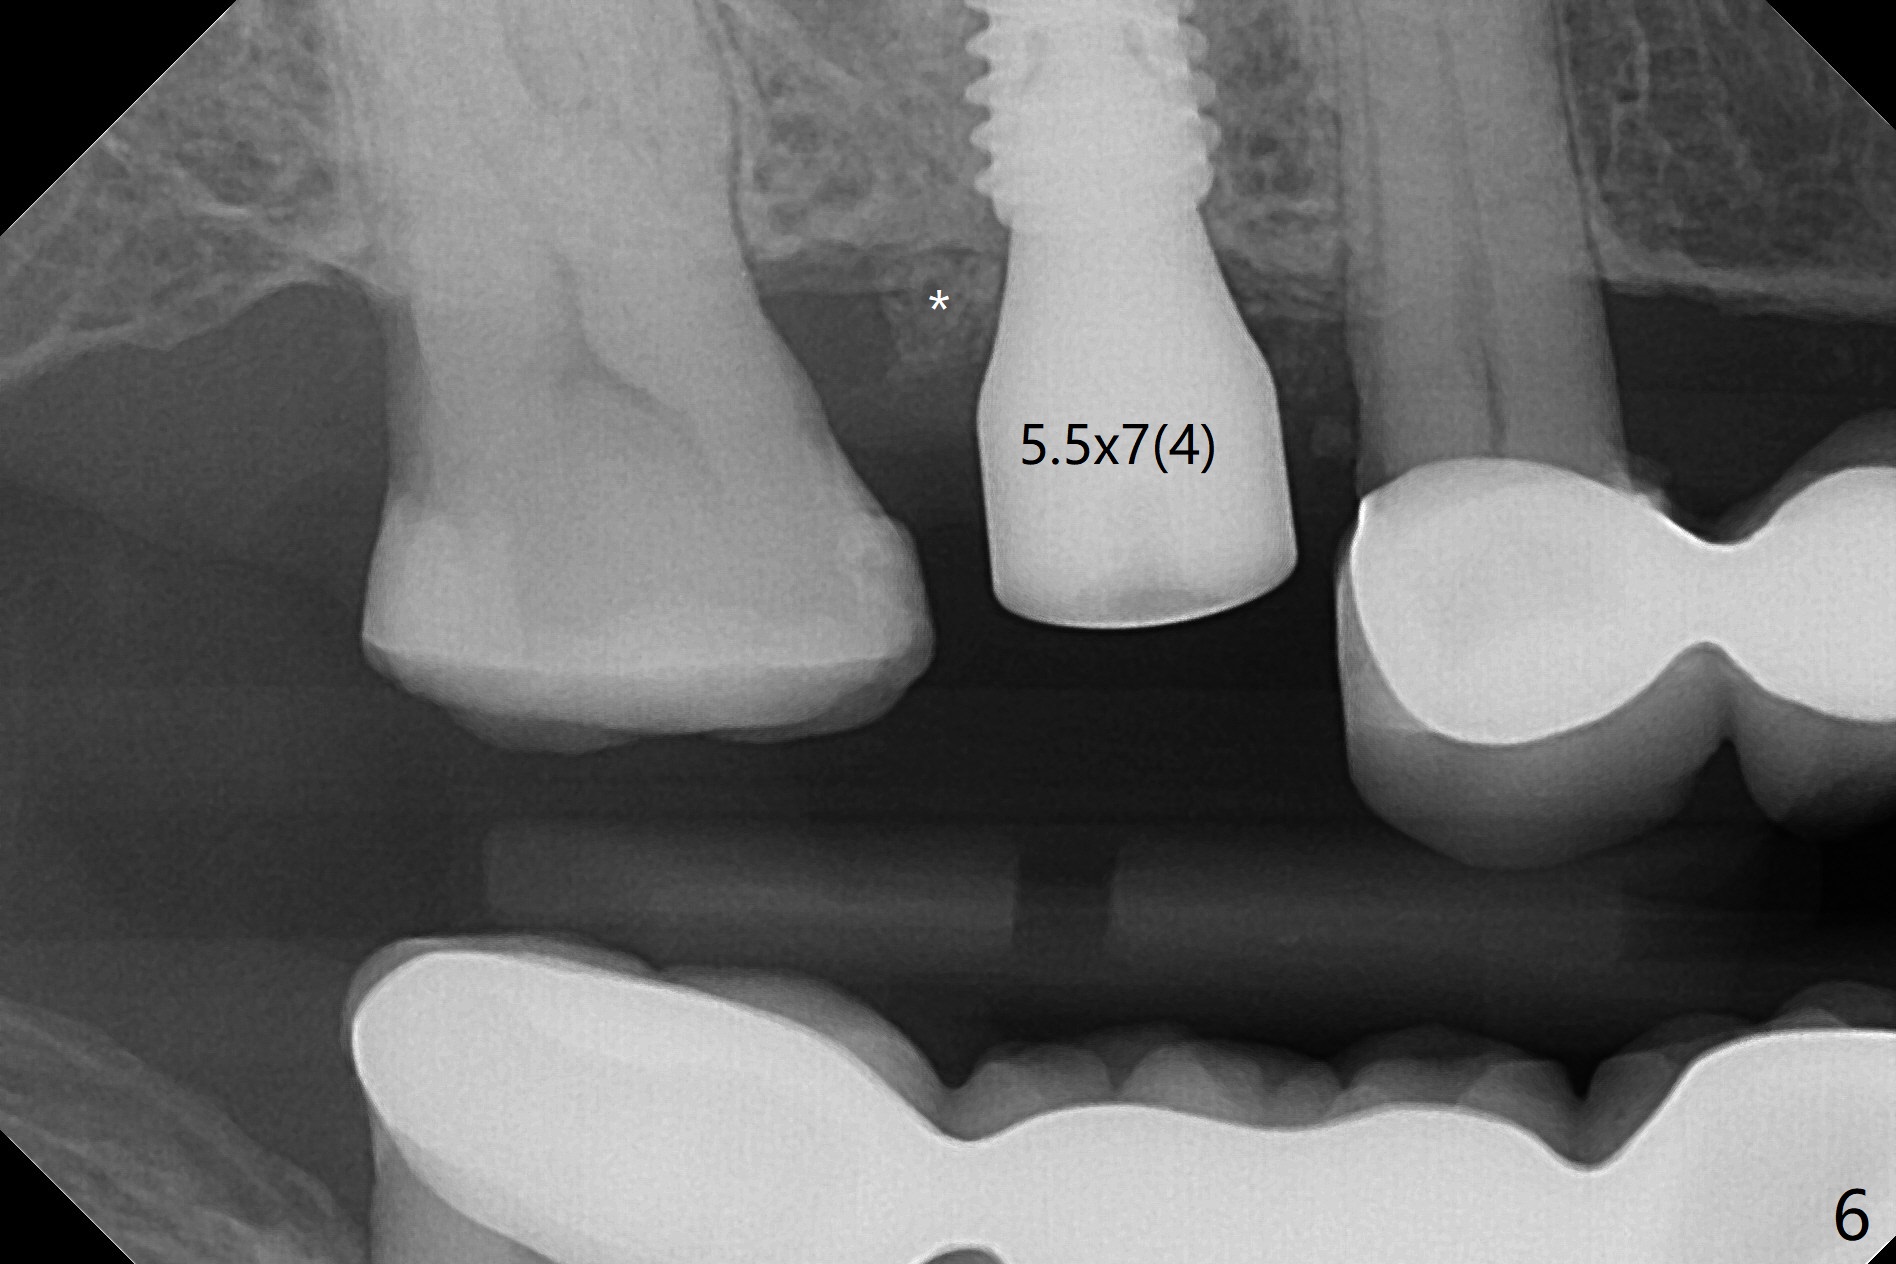

提取上清液后,红管再次离心,同样速度,5分钟,便形成PRF(胶状,上面黄色部分,图七),由于试管在离心机放置角度缘故,PRF与下面红血球部分(深色)交界处是一个斜面,制作PRF膜前,必须在交界处下面剪(图八白斜线),因为在交界处有效成分浓度最高,请看录像(虽然剪的太高些)。制作完毕的PRF膜可以覆盖图四骨块表面,但是用于图一之后,塞入上颌窦(录像),目的促进上颌窦膜修复,万一提升时出现隐形破裂。术后五个月放置5.5x4(4)毫米基台,未完全就位:基台与植体之间有间隙(图九:>),可能牙槽嵴阻挡(*),直径小的基台容易就位(图十),植体根尖空间(上下)也缩小(图十一)。